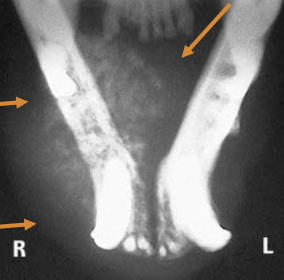

majority invades bone (locally invasive)

How is oral SCC in dogs staged?

LN evaluation, thoracic imaging

occasiona lmetastasis, common bone involvement often the hard palate